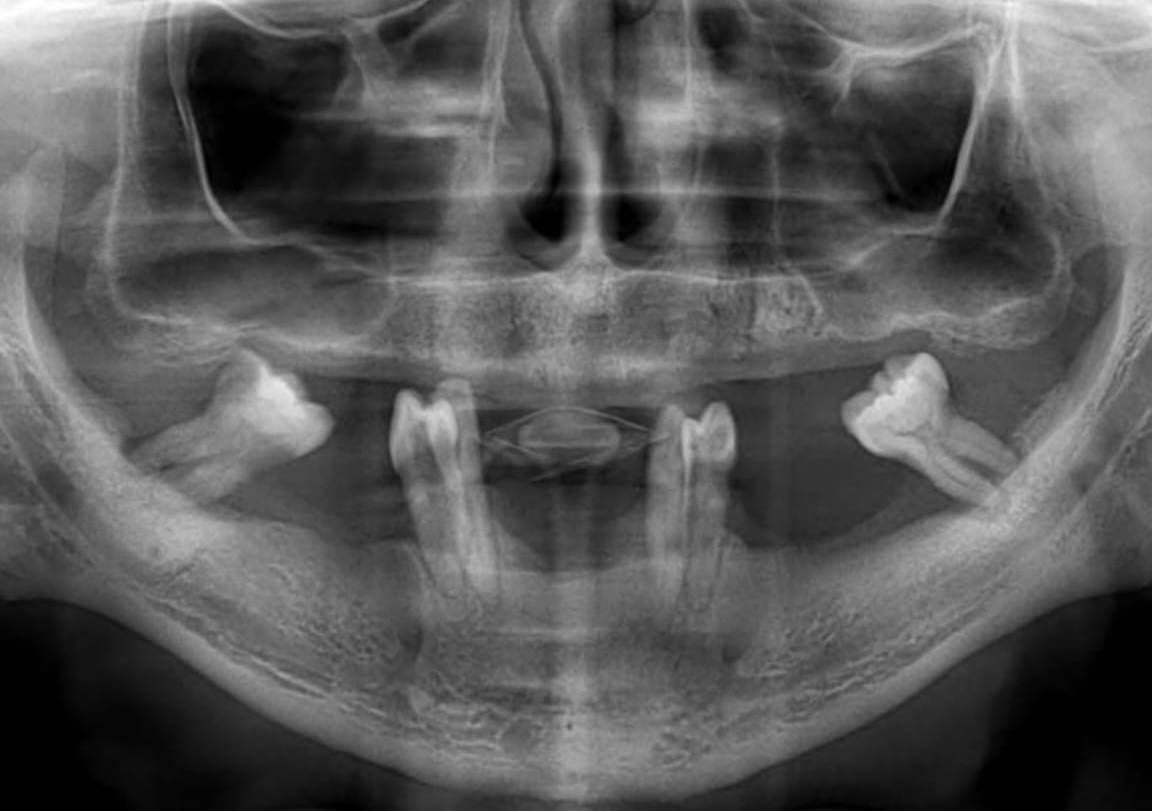

1. Digital Scanning and Planning

A 3D tomographic image of the jawbone is taken.

The bone surface is modeled with millimetric precision from this image.

The skeletal structure of the subperiosteal implant is custom-designed using CAD/CAM technology.

2. Production (Titanium Structure)

The design is produced from titanium in the laboratory using a three-dimensional printer (3D printer).

This structure is prepared to be 100% compatible with the patient's jaw anatomy.